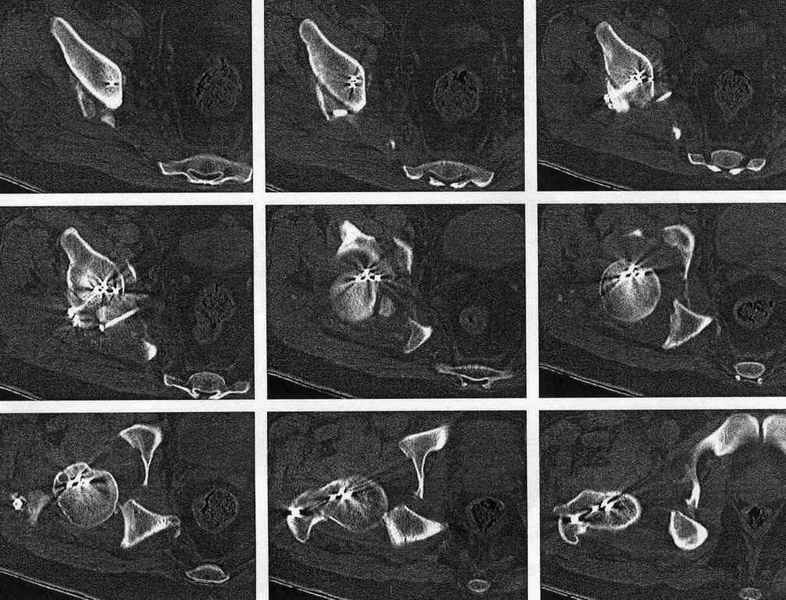

После установления вывиха бедра через 3 недели после травмы больному выполнена попытка открытой репозиции, остеосинтез вертлюжной впадины, Бедро фииксировано трансартикулярно спицами. После операции неврит седалищного нерва. В течение ещё 3-х недель после операции установлено что отломки не репонированы, вывих бедра не устранён (см. КТ и рентгенограмму), неврологической динамики нет. Возние вопрос о повторном оперативном вмешательстве по поводу чего разгорелись жаркие споры и сформировалось следующие мнения:1. Тотальное эндопротезирование с цементной фиксацией чашки протезом "ЭСИ" (другого протеза нет)2. Повторная открытая репозиция бедра с замещением дефектов вертлюжной впадины аутокостью с целью подготовки для последующего эндопротезирование. Предполагается фиксация тазобедренного сустава в послеоперационном периоде гипсовой повязкой или аппаратом внешней фиксации.Прошу высказать ваше мнение о тактике дальнейшего лечения пациента, о предложенных вариантах. Отдельный вопрос о возможности первичного тотального эндопротезирования при ацетабулярных переломах. (Лечащий врач настаивал перед первой операцией на выполнении тотального эндопротезирование с цементной фиксацией чашки через 3 недели после травмы)

Представленный перелом вертлужной впадины характеризуется нарушением непрерывности тазового кольца, обусловленный переломом передней и задней колонн, вполне возможно и с повреждением weightbearing surface- по прямой рентгенограмме сложно однозначно судить, а представленные томограммы не захватывают несущую поверхность впадины. Экспресс протезирование однозначно не показано - фиксировать ацетабулярный компонент не к чему, а цемент *уйдет* в зоны перелома. Достаточно обширное вмешательство должно быть направлено на восстановление целостности тазового кольца(передний забрюшинный доступ) и фиксация реконструктивной пластиной, после чего пациент поворачивается на бок или на живот и на тракционном столе из заднего доступа фиксируется задняя колонна реконструктивной пластиной. Для репозиции фрагментов нужно иметь тазовые зажимы (pelvic reduction clamps), без которых достичь желаемого результата технически сложно. Оптимальное время хирургии через неделю, 10 дней , когда общее состояние больного стабилизируется и закончено активное кровотечение из отломков. Хорошо бы иметь cell saver для таких случаев, а если нет - интраоперационная гемотрансфузия донорской крови.

Было бы существенным посмотреть обзорную R-грамму до операции. По данным послеоперационных снимков и КТ имеется низкий двухколонный перелом или

высокий Т-образный перелом с отрывом свода. Для уточнения необходиы косые проекции (Judet). Весь ли седалищный нерв молчит или только м/б порция?